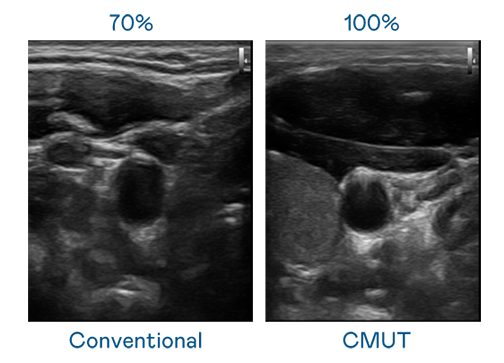

CMUT 技术是一种用电容式微机电元件来产生超音波讯号的技术。与传统 PZT 压电式技术相比,CMUT 频宽增加 30%,更宽频的超音波讯号让影像解析度大幅提升,是实现高影像品质医疗超音波扫描、促进精准医疗发展的关键技术。

超音波影像的解析度高低,首先取决于探头能发出的讯号频宽。利来国际w66 CMUT 可提供高清晰的超音波讯号,提供高频宽、高灵敏度、影像纹理细节更高的超音波影像,协助医护人员缩短影像判读时间及利用精准的医疗影像进行诊断。